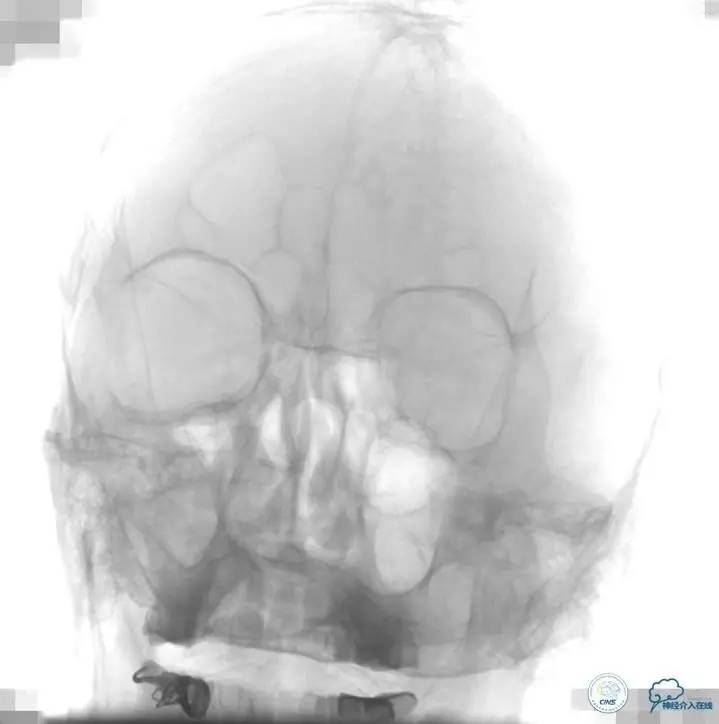

▼L-CCA

▼R-VA